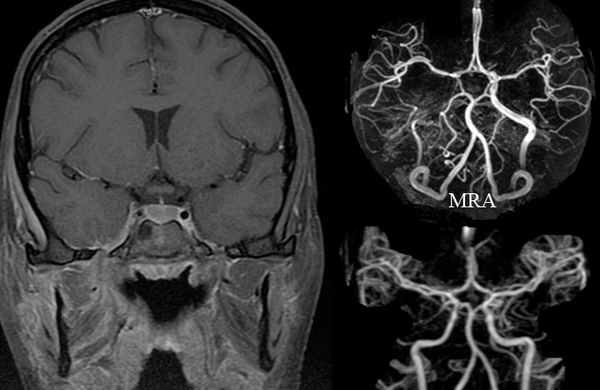

МРТ и МРА головного мозга. Тромбоз левого кавернозного синуса.